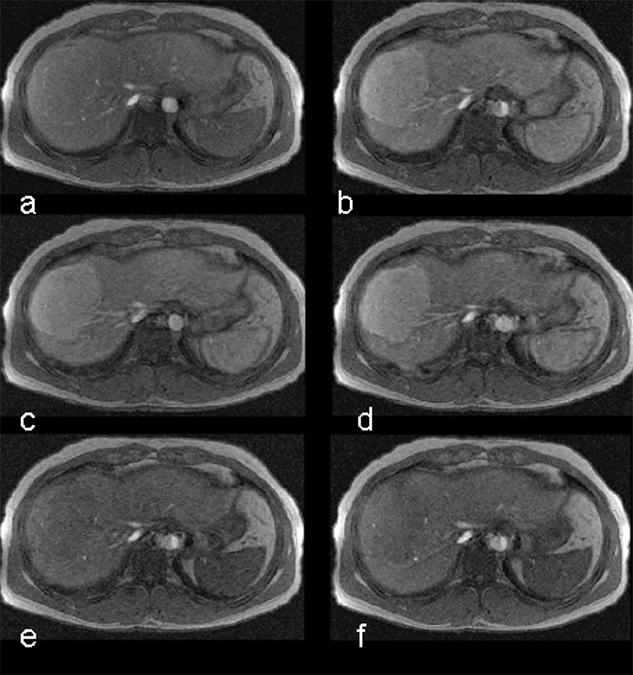

Figure 13-16:

The uptake of Mn-DPDP (mangafodipir) in the liver relies on the ability of hepatocytes to excrete metal ions. Manganese separates from the DPDP-complex and is taken up by the hepatocytes.

T1-weighted GRE images. (a) The metastases are well delineated 15 minutes after the injection, and (b) even 24 hours after administration some of the contrast agent remains.